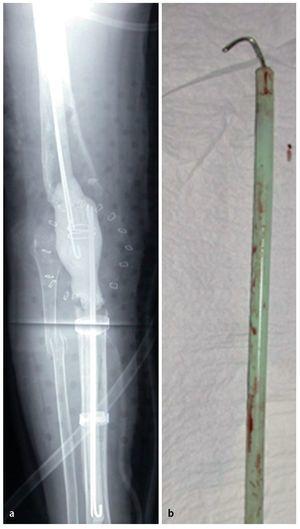

Fig. 9 a) Radiografía de un espaciador para el puenteo de defectos con fijación de la cavidad medular. b) Detalle del clavo de cemento integrado en el cemento PMMA (agujas de perforación revestidas con cemento PMMA). El espaciador se dimensionará delgado, de modo que sea posible el cierre de la herida libre de tensiones por encima del drenaje. La existencia de grandes partes de defectos óseos comporta una inestabilidad absoluta de la pierna, que no se puede estabilizar con ortesis. Es posible aplicar un fijador externo; sin embargo, tiene el inconveniente de crear una unión permanente con la cavidad medular desde fuera («pin track»). Por otra parte, aumenta el riesgo de infección para la futura prótesis. Estas franjas de defectos se pueden puentear con espaciadores para médula espinal fabricados de PMMA.